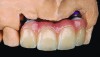

Fig 1. Preoperative (Fig 1), preparation (Fig 2), and final postoperative (Fig 3) images of a two-unit CL-I feldspathic veneer case.

Figure 1

Fig 2. Preoperative (Fig 1), preparation (Fig 2), and final postoperative (Fig 3) images of a two-unit CL-I feldspathic veneer case.

Figure 2

Fig 3. Preoperative (Fig 1), preparation (Fig 2), and final postoperative (Fig 3) images of a two-unit CL-I feldspathic veneer case.

Figure 3